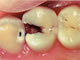

![]() (シーツー) |

少ししみる、黒く穴があいている むし歯の範囲はエナメル質を超えて象牙質まで及び穴があいている。 冷たいものがしみたり、食事中に物を噛むと痛いなどの症状が現れることもある。 |

・小さめの穴、または前歯

→コンポジットレジン修復 ・大きめの穴や歯と歯の間

→インレー修復 (保険治療では銀色の金属の詰め物) |

![]() ![]() X線写真でむし歯の進行が わかりました。 |